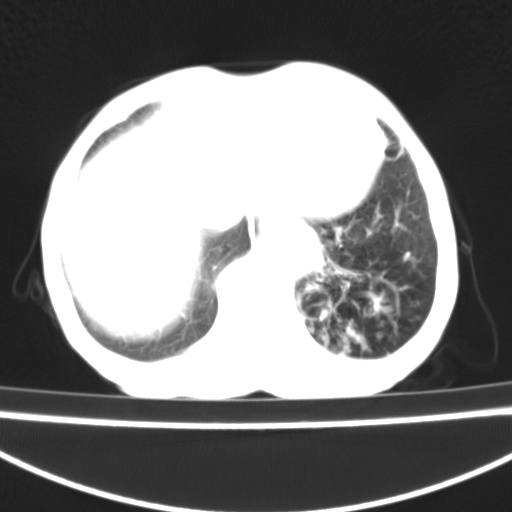

患者 女 67岁,反复咳嗽咳痰2年,加重伴喘及双下肢浮肿1月

陈旧性肺结核、慢性支气管炎、支气管扩张症、肺心症、肺动脉高压。

诸大血管及f肺门血管增粗迂曲.左下肺多发薄壁空腔影.部分非也透亮度增高.薄曾扫描可区分肺气肿类型.考虑1.慢性支气管炎 2.左下肺支气管扩张 3.肺气肿 4 肺动脉高压5.是否有先心病病史

考虑1.慢性支气管炎 2.左下肺支气管扩张 3.肺气肿 4 肺动脉高压

慢支炎、肺气肿、双肺感染、左下囊状支扩。

慢支、肺气肿、肺动脉高压;左下肺囊状支扩并粘液栓形成。